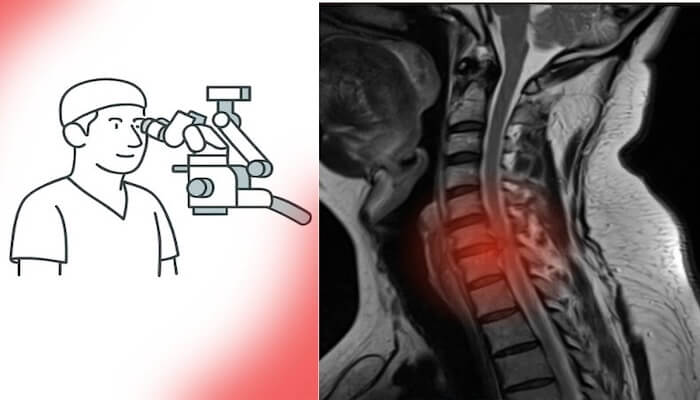

Beyin ve omurga cerrahisinde son yıllarda yaşanan teknolojik ilerlemeler, cerrahiye bakış açısını tamamen değiştirdi. Artık ameliyatlar daha küçük kesilerle, daha az kan kaybıyla ve çok daha kısa iyileşme süreleriyle gerçekleştirilebiliyor.

Mikrocerrahi, endoskopik cerrahi ve nöronavigasyon sistemleri sayesinde sinir dokuları korunarak işlem yapılabiliyor. Bu da hem cerrahi güvenliği artırıyor hem de genç hastaların ameliyat kararını kolaylaştırıyor.

Eskiden korkulan “uzun iyileşme süresi” veya “kalıcı hasar riski” gibi endişeler, yerini yüksek başarı oranlarına ve hızlı dönüş sürecine bıraktı. Özellikle bel fıtığı ameliyatı, boyun fıtığı ameliyatı ve beyin tümörü ameliyatı gibi operasyonlar artık minimal invaziv yöntemlerle çok daha kısa sürede tamamlanabiliyor.

Ameliyat mikroskopları, nöronavigasyon sistemleri, intraoperatif monitörizasyon ve endoskopik teknikler sayesinde cerrahlar artık milimetrik düzeyde güvenle çalışabiliyor. Bu da komplikasyon riskini belirgin biçimde azalttı.

Ayrıca uzun yıllara dayanan klinik tecrübe, hasta seçimi ve ameliyat planlamasında büyük bir hassasiyet kazandırdı. Doğru endikasyonla yapılan erken cerrahiler, özellikle bel fıtığı ameliyatı ve boyun fıtığı ameliyatı gibi girişimlerde daha hızlı iyileşme, daha az ağrı ve kalıcı sinir hasarını önleme açısından büyük avantaj sağlıyor.